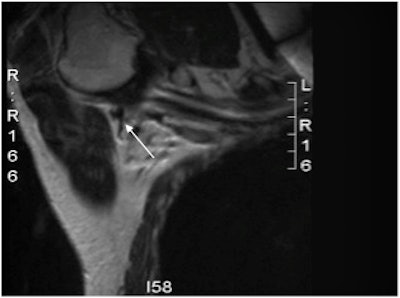

An axillary MRI following the administration of subcutaneous SPIO into the breast (Endorem, Guerbet). The lymphatic tract is seen to go into a lymph node. Image courtesy of Mr. Michael Douek.In addition, 34% of normal-appearing nodes are positive for malignancy, which begs the question of how best to target axillary nodes for core biopsy.

Ahmed and colleagues posit that noninvasive MRI options, such as axillary MRI, diffusion-weighted imaging (DWI), and SPIO-enhanced MRI, would be more useful. Specifically, data from studies using SPIO indicate that the technique has sensitivity and specificity for detecting axillary involvement of 98% and 96%, respectively.

SPIO injected interstitially into the periareolar region of the breast has been successfully used to guide SLNB. In a previous study, Johnson and colleagues showed 13 nodes containing metastases had variable quantities of iron within them, but the iron was not present in the areas of the node containing the metastasis (Histopathology, February 2013, Vol. 62:3, pp. 481-486).